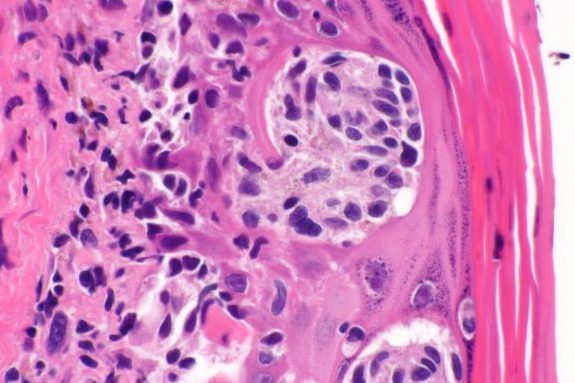

I 3 tipi principali di tumori cutanei

Non tutti i tumori cutanei sono uguali. Conoscerli aiuta a capire il rischio.

1. Basalioma (BCC)

Il tumore cutaneo più comune. Cresce lentamente e metastatizza molto raramente. Si presenta come una “perla” rosa, una lesione traslucida o una ferita che non guarisce. Rischio Basso.

2. Spinalioma (SCC)

Il secondo più frequente. Può crescere più rapidamente del BCC e ha un rischio moderato di metastasi. Si presenta come un nodulo duro, una crosta persistente o una lesione ulcerata.

Rischio Moderato.

3. Melanoma (MC)

Il più raro ma il più pericoloso: può dare metastasi rapidamente se non diagnosticato precocemente. Nasce da un neo esistente o da pelle sana. Rischio Alto.